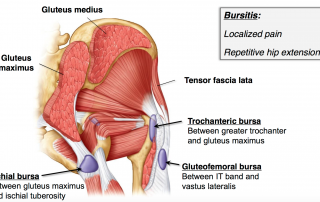

Ischial Bursitis

There are two types of hip bursitis. Ischial Bursitis which is a swollen bursa near where your hamstring attaches on your Ischial Tuberosity (SITS bone) and Trochanteric Bursitis which is where your [...]